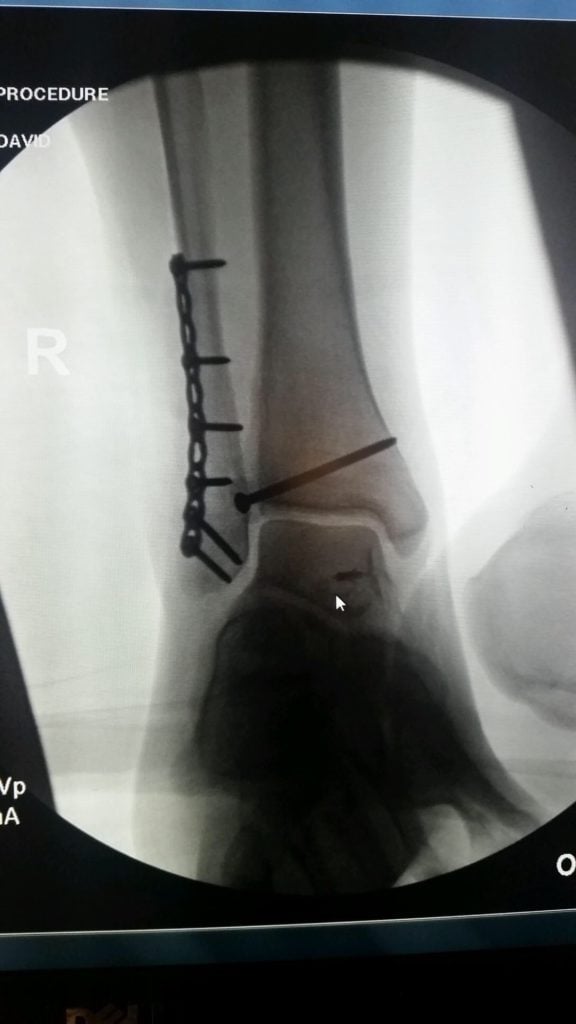

In October 2016 I was knocked over during a night out in New York City and dislocated and fractured my ankle. The following week, I went to HSS and met with Dr. Wellman. Right away he was very positive and optimistic with my options. He was able to fit me into his schedule four days later (10/24/2016) and inserted eight screws and a plate into my ankle. I have been going to PT at HSS for the past three months, seeing Erica Fritz. One month after surgery I was walking on my own without a boot or crutches. I am now able to walk and run without any pain! Thanks to everyone at HSS that has helped be get back on my feet so quickly!